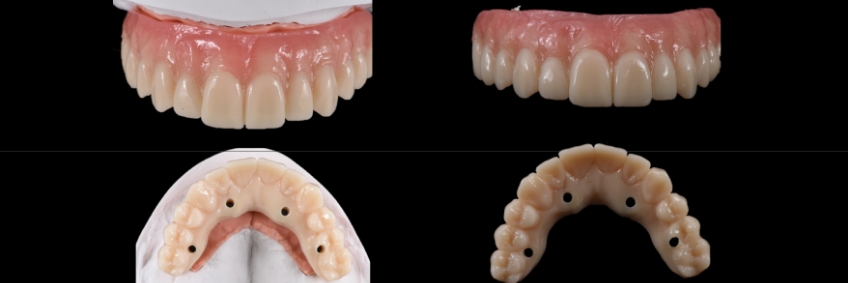

This visual essay shows, through a series of images, the fabrication of a maxillary implant-supported fixed dental prosthesis. The SRA abutments of the anterior implants were changed to optimize the definitive implant-supported fixed dental prosthesis design.

In this visual essay, we have outlined the steps in the fabrication of a maxillary full arch implant-supported prosthesis solution where the SRA abutment needs to be changed because the orientation of the screw access hole in the provisional restorations seems too palatal from an ideal position, thereby underlining the importance of analyzing these aspects during the provisional phase and correcting the angulation of them to provide a more ideal design and increase the long term predictability of the prosthetics.